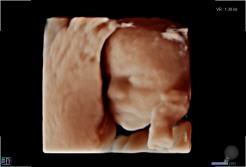

Seit März 2019 steht ein neues 3D/4D-Ultraschallgerät für faszinierende Eindrücke von Ihrem Baby zur Verfügung.

Außer den Fotos können auch 3D/4D Viedeoclips gemacht und auf einem USB-Stick gespeichert werden. So können die Bilder und Clips jederzeit angesehen werden.